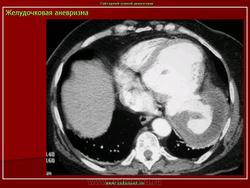

Аневризма левого желудочка